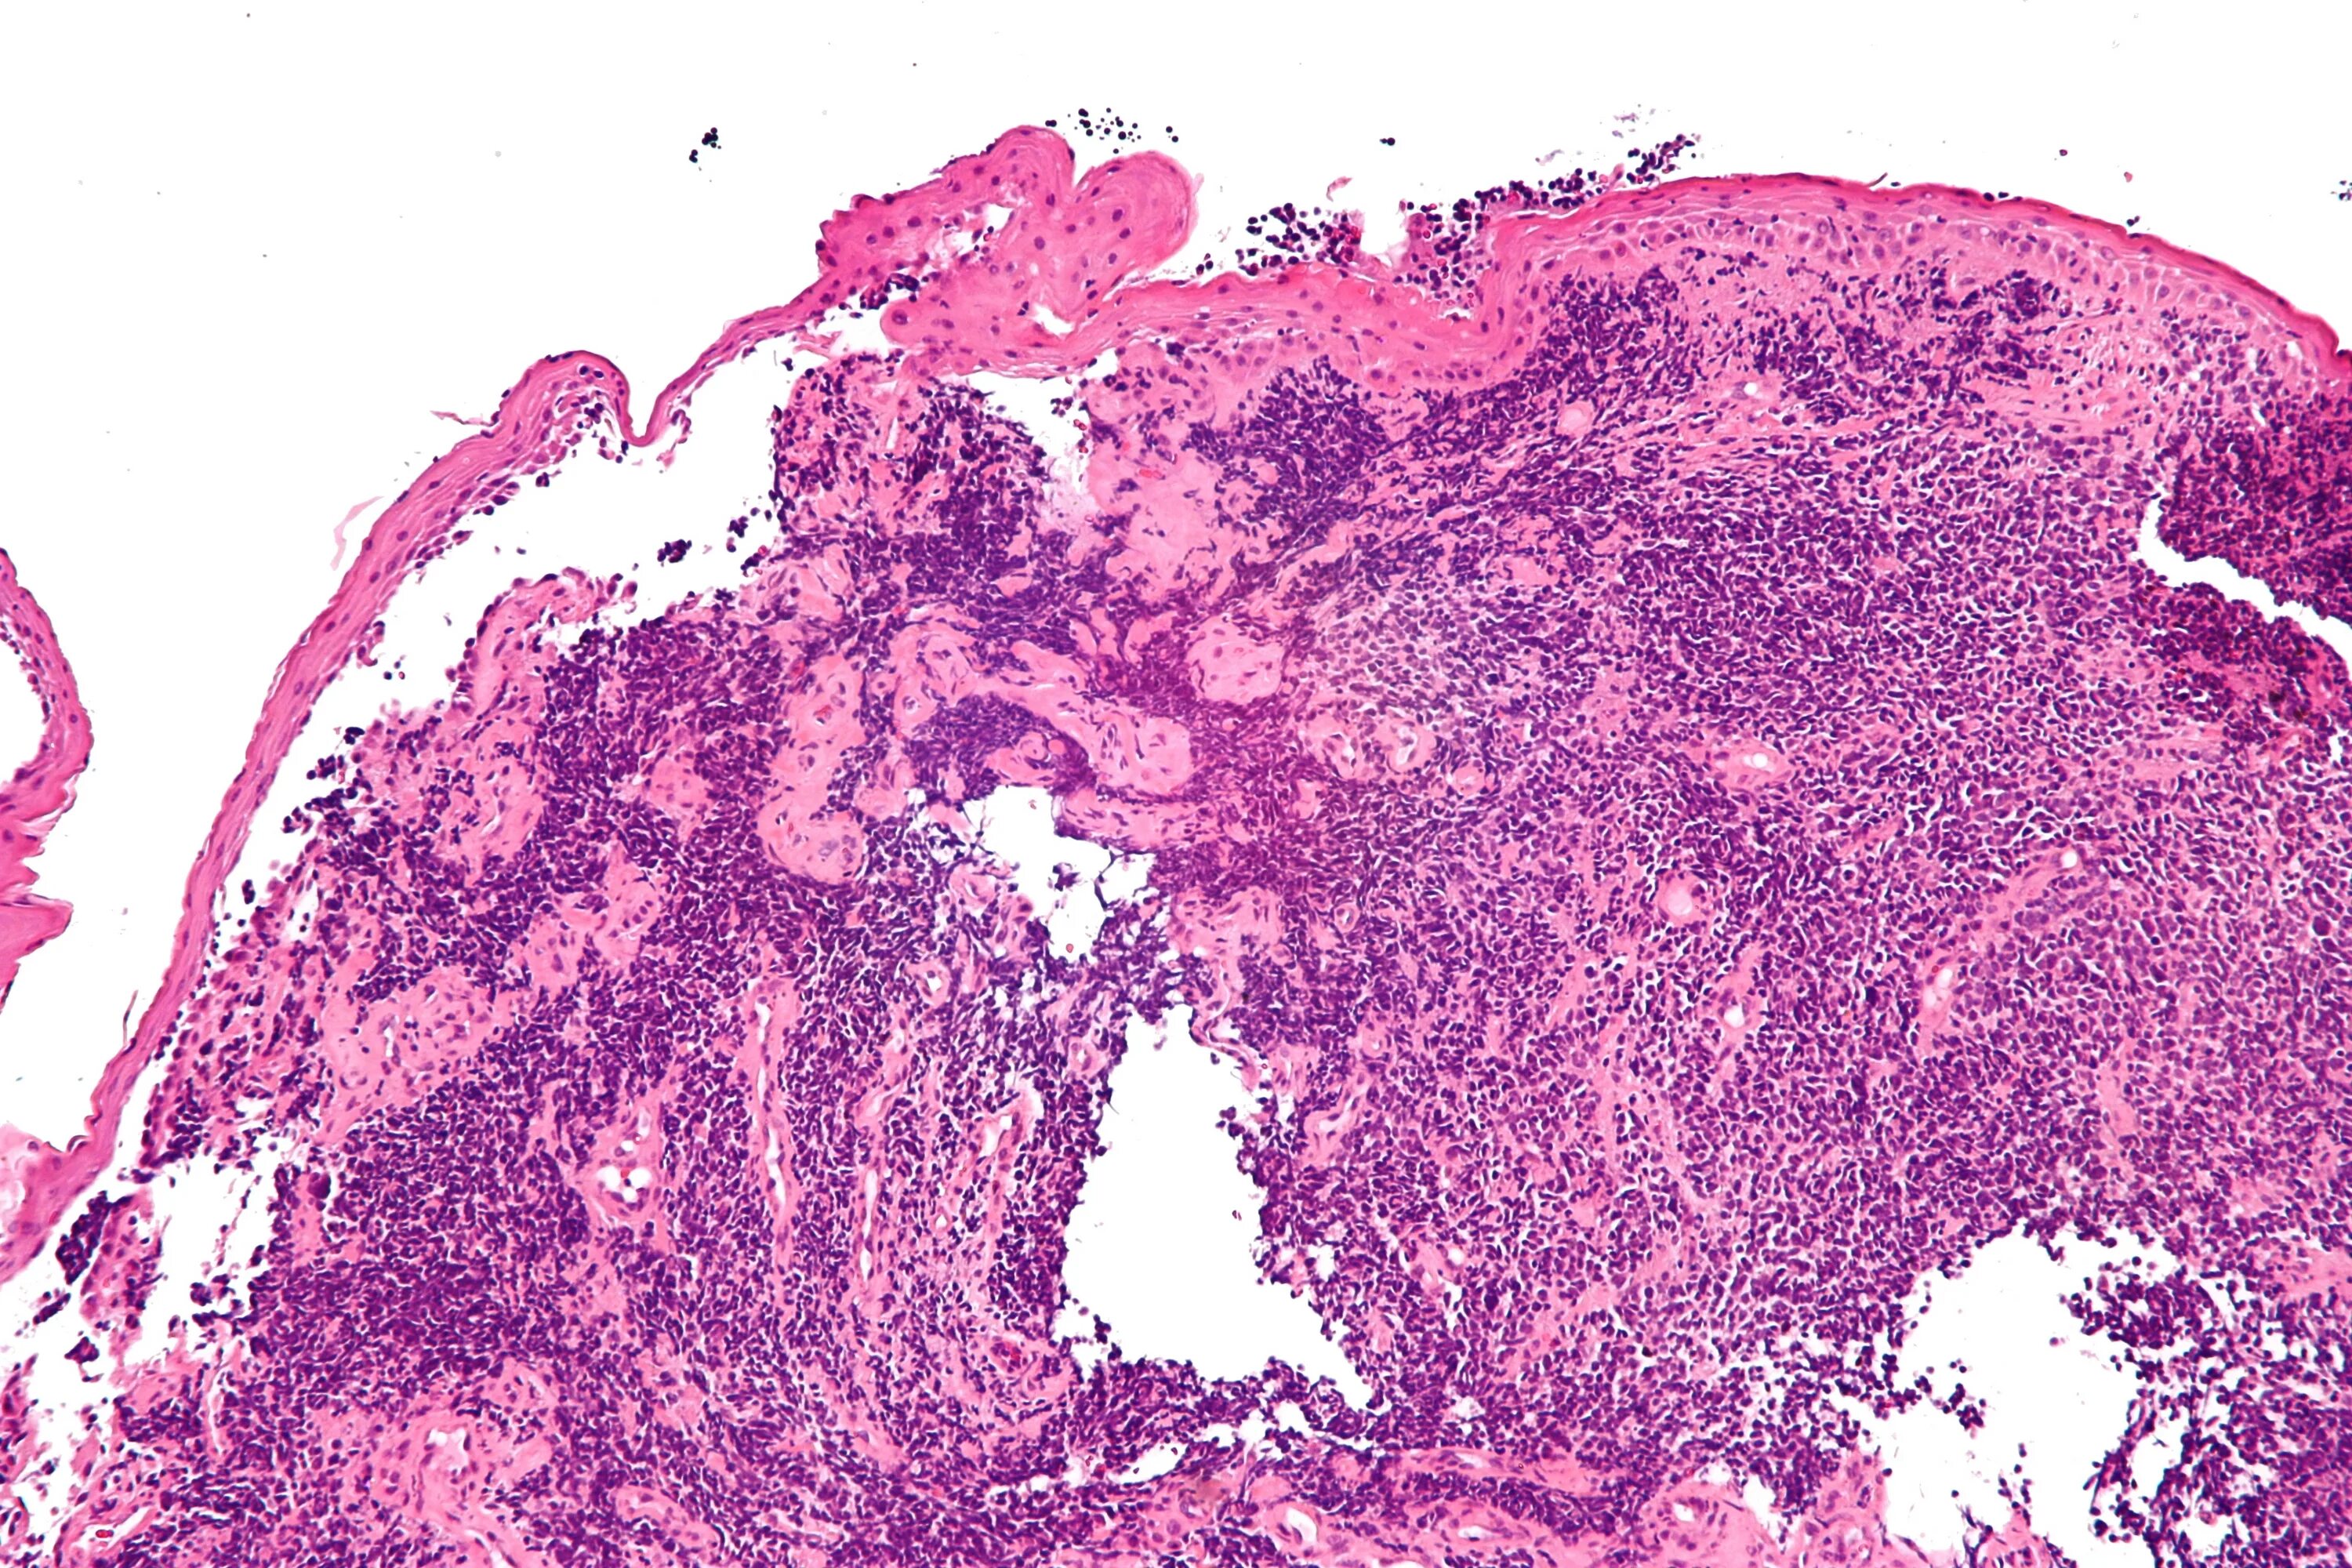

Рак легкого гистологические